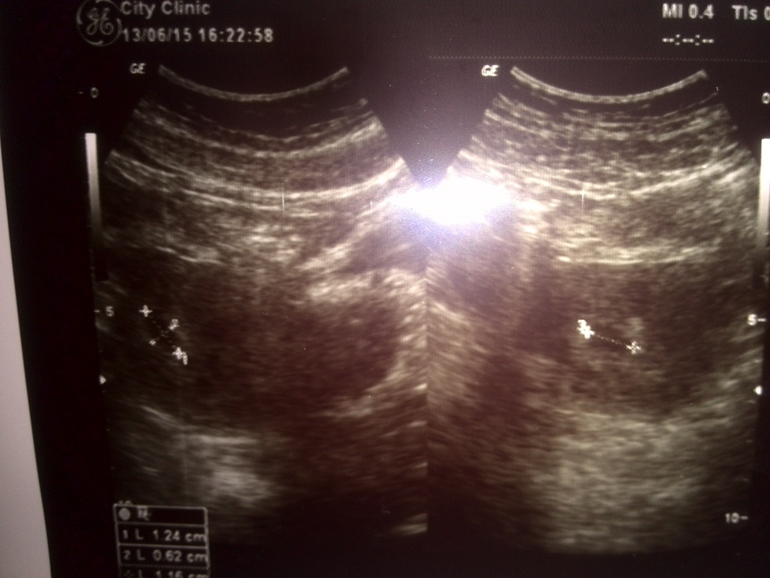

вот наше узи

Фолликулометрия5 недель 5 дней...пока только ПЯ 10,1мм (эмбриона,желточный мешочек не увидели)...в понедельник к гине и строго все по ее рекомендациям теперь